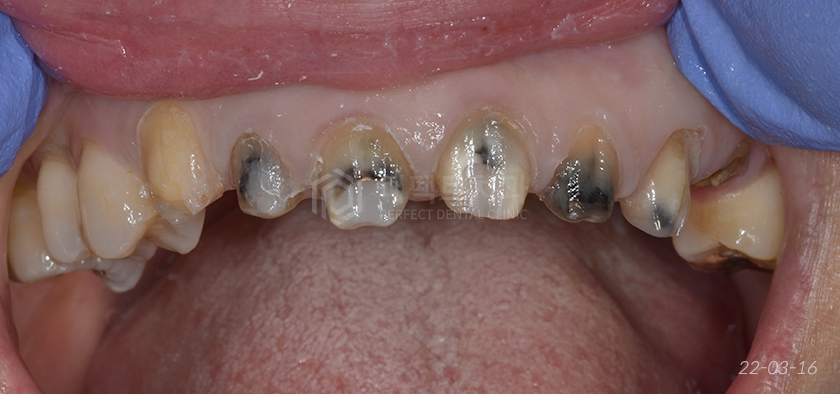

기존 보철물 제거 후

벗겨낸 상태 그대로의 사진입니다. 변색과 2차충치, 거의 남아있지 않아 발치가 필요한 치아까지 한 눈에 보입니다.

당연히 이런 상태에 보철을 그대로 씌워서는 안됩니다. 충치를 치료하지 않고 덮어버리게 된다면 이후 더 큰 문제가 되겠죠?

심지어 안에 충치가 보철에 비쳐보일 것이기 때문에 제대로 치료를 하고 이후에 보철물을 씌워줘야 합니다.

그래서 2차 충치를 전부 제거하고 떼우는 작업을 거치고 잇몸 성형도 해서 좀 더 깔끔하게, 좀 더 심미적일 수 있게 진행하기로 하였습니다.